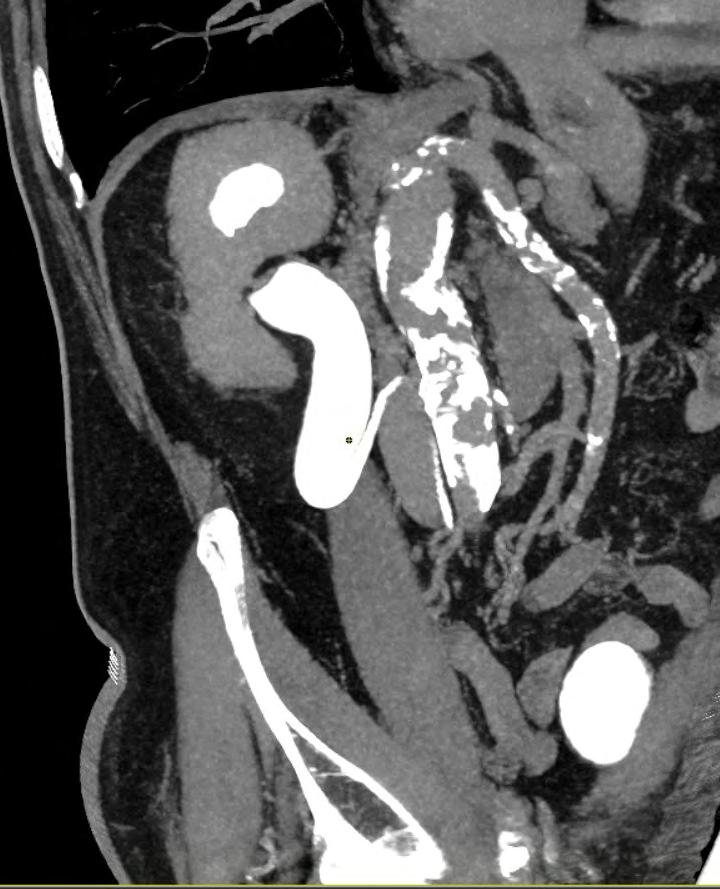

Retrokavální ureter

Retrocaval ureter

Alexandra Kucserová, Hynek Skoták, Milan Král, Daniela Tomášková, Zbyněk Tüdös